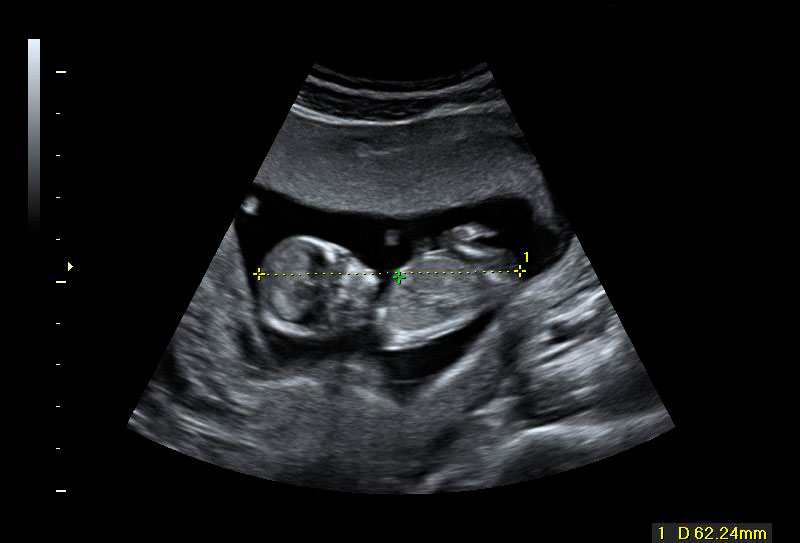

La ecografía de la derecha muestra a un bebé con un cribado positivo que resultó tener un síndrome de Down. La translucencia nucal (o pliegue nucal) por ecografía se ve como un espacio negro en la parte posterior del cuello, acotado por las marcas del ecografista. El bebé de la izquierda tiene una translucencia nucal normal.